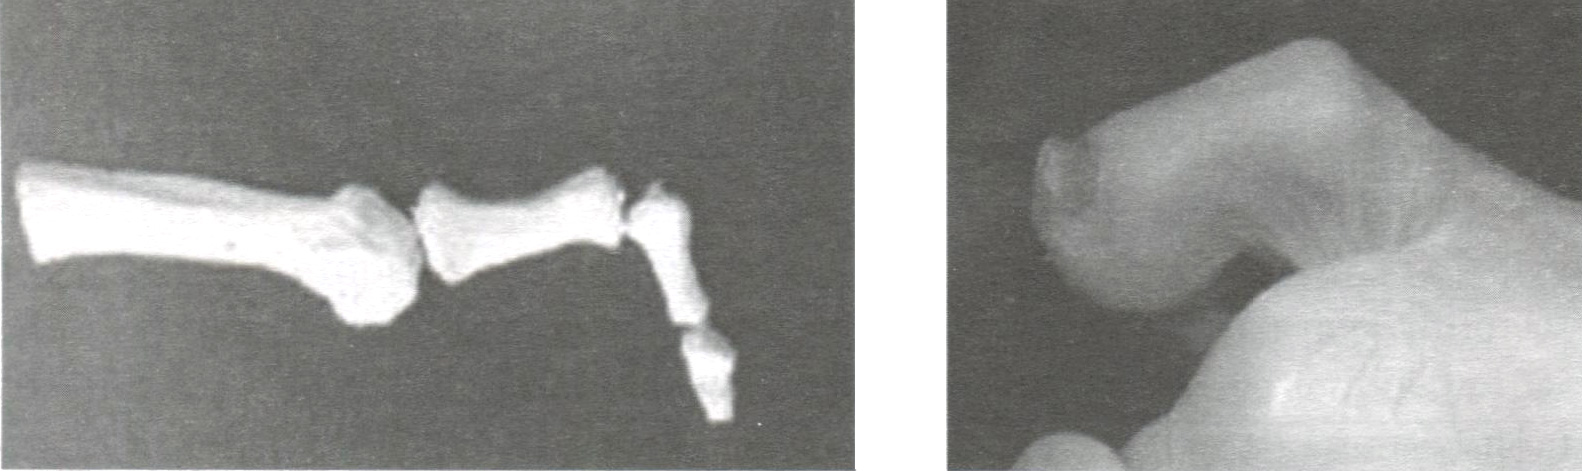

Первые два варианта характеризуют сгибательную деформацию пальцев. Под термином hammer toe (рис. 15) подразумевается сгибательная деформация в проксимальном межфаланговом суставе (PIP flexion).

Рис. 15. Сгибательная молоткообразная деформация пальца - hammer toe (PIP flexion)

Сгибательная деформация в дистальном межфаланговом суставе (DIP flexion) известна в зарубежной литературе как mallet toe (рис. 16). В классификации М.И. Куслика сгибательной деформации соответствуют I и II степени (в случае нефиксированной деформации — I, в случае фиксированной деформации — II степень).

Рис. 16. Сгибательная молоткообразная деформация пальца - mallet toe [DIP flexion)